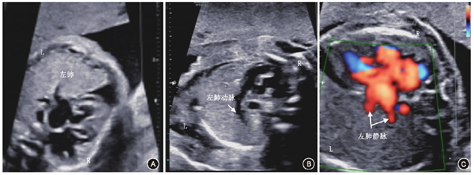

该孕妇于2019年7月2日(孕28周+1)在本院复查B超示:双顶径74.2 mm、头围265.1 mm、腹围224.5 mm、股骨长53.8 mm、肱骨长47.5 mm、羊水指数95 mm;胎心率142次/min,胎盘厚度27 mm;胎儿左肺面积8.8 cm2,心尖部见深约6 mm液性暗区(图2)。该孕妇于孕30周在外院行胎儿胸部MRI检查,再来本院就诊时自诉结果提示"与超声相符",但未能提供相关资料和报告。之后孕妇定期在外院产前检查,未见其他明显异常。